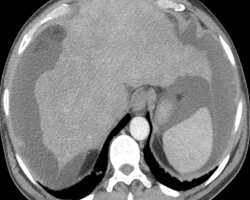

Cirrhose